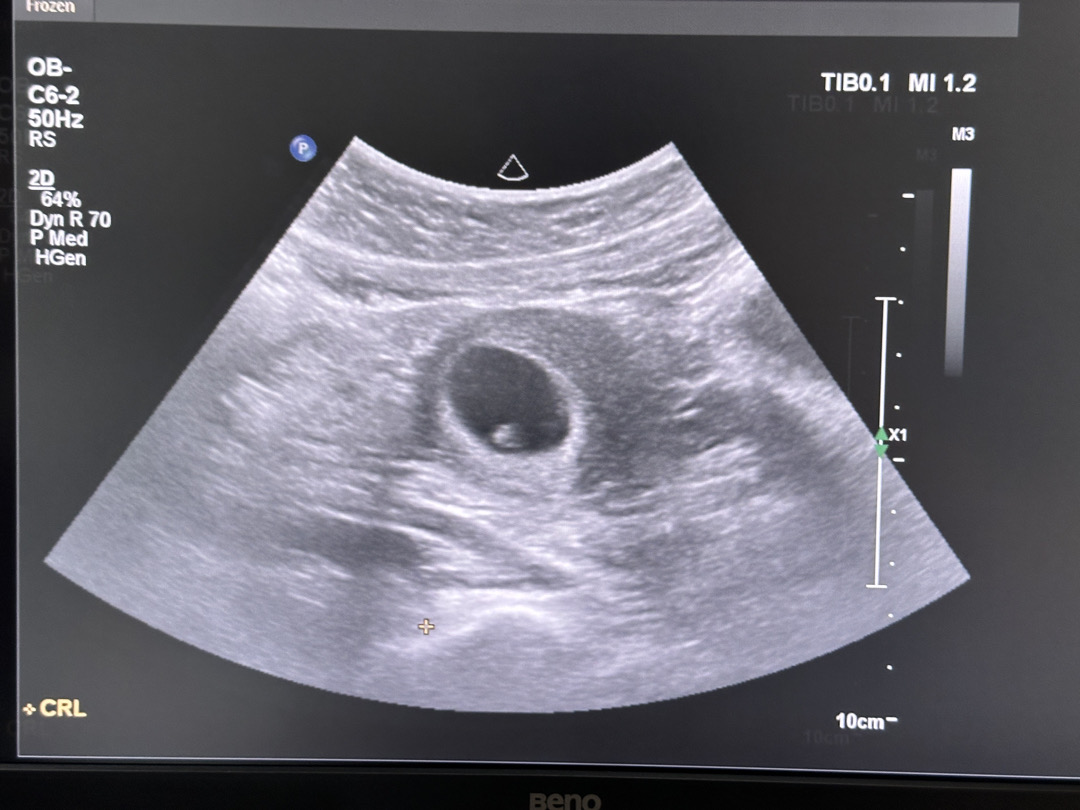

안녕하세요! 임신 사실 알고 한 달 꾹꾹 참고 오늘 병원 다녀왔어요~! 막생 6/28이라 네이버주수로는 6주3일에 갔는데 애기크기로는 5주6일 이라고 하더라구요~ 처음에는 질초음파로 보는데 아기집만 보이고 아무것도 안 보여서 걱정 하다가 선생님이 배초음파로 바꾸시더니 아기랑 난황이 잘 보였어요~! 아직 작지만 심장소리까지 듣고 왔습니다! 아기집 크기랑 아기 크기나 모양도 다 정상이라고 하네요! 한 번 유산 하고 초음파로 처음 좋은 소식 들어서 정말 감사하네요!! 4월 베동 어머님둘 같이 화이팅 합시다!